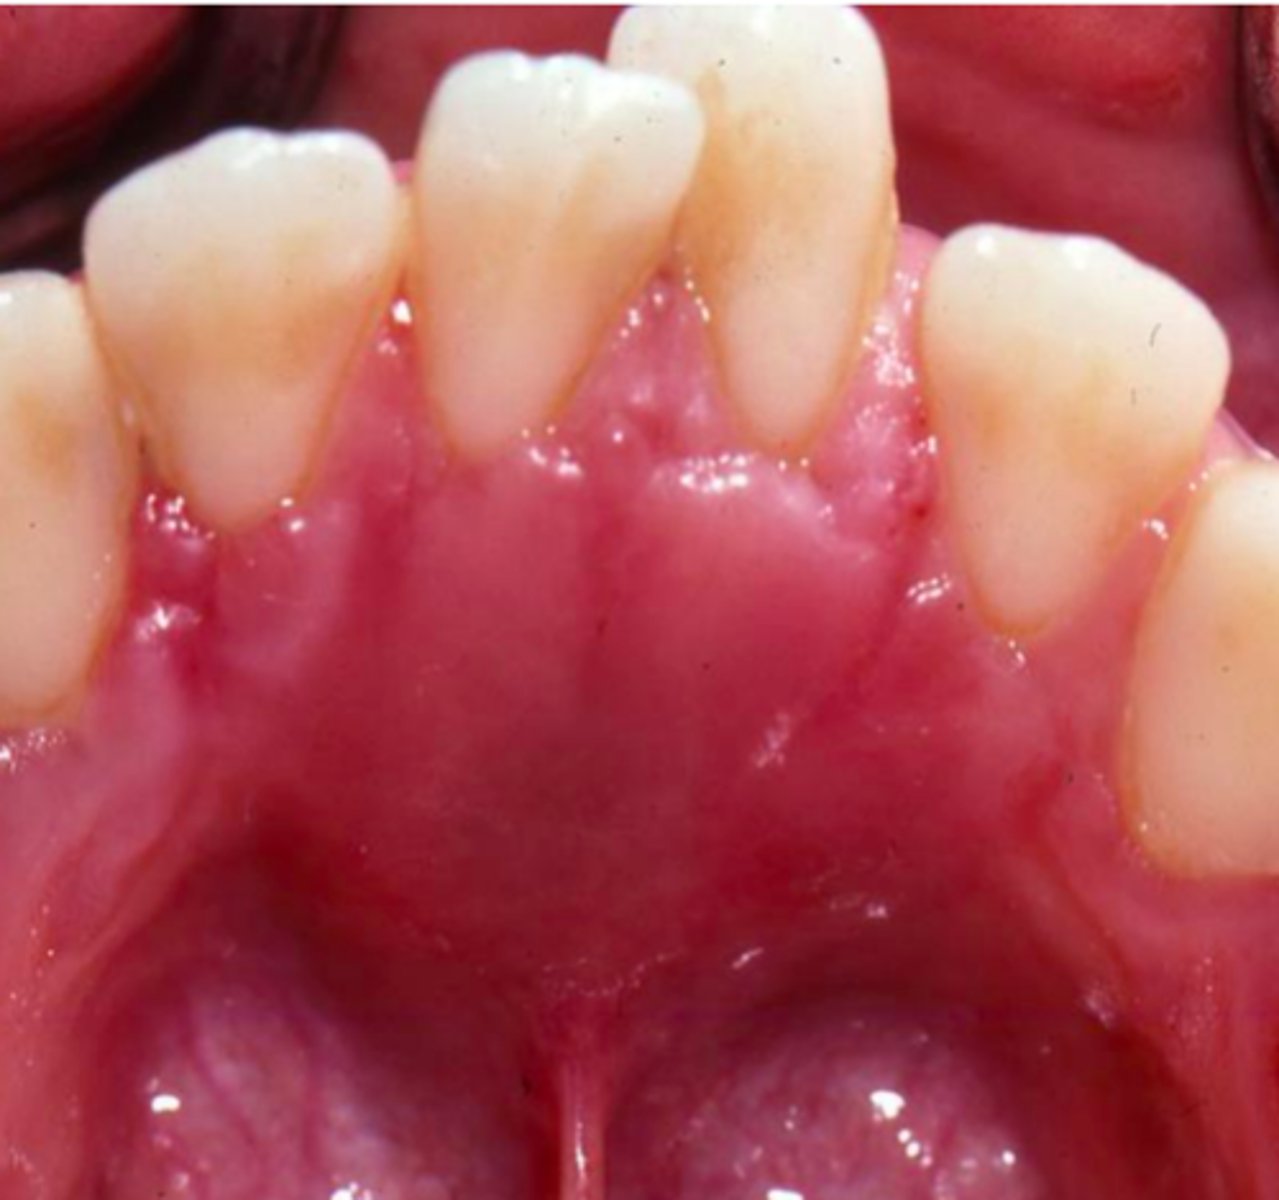

What is a peripheral ameloblastoma?

ameloblastoma of gingiva

⢠central = lesion in bone, peripheral = lesion in soft tissues

⢠RARE presentation of ameloblastoma

ā most odontogenic cysts/tumors can have peripheral presentations

⢠little to no bony involvement

⢠not as invasive

⢠treatment = surgical excision

⢠prognosis = excellent - recurrence is rare